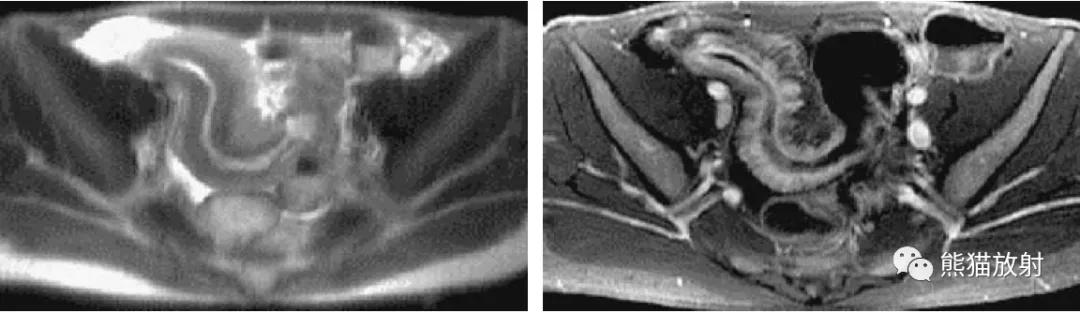

直肠周围脓肿(易误诊为直肠癌)。4个月前因增生行前列腺切除术,出现便秘。盆腔CT显示直肠病变并管腔变窄(箭头)。T1和T2加权图像显示直肠壁增厚和周围充满液体的结构(箭),提示脓肿或坏死性肿瘤。